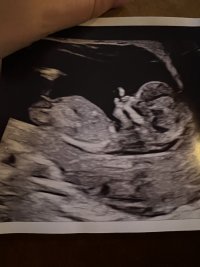

Jeg vil si tidlig jente her, det er fremdeles tid for at den vil reise seg også ser jeg ikke helt hvor blæra er. Nuben har ikke tydelig stacking og er veldig parallell til ryggraden, men det er noe over nuben som kan være et ben eller noe som kan være stacking in progress, det vet jeg ikke, men det er fremdeles tidligVet ikke om det er bein eller nub på dette bilde, noen som kan si noe? De ville ikke si noe på sykehuset i dag. Fra en annen vinkel så man bare en liten tutt som hun sa kunne være både gutt og jente, men har ikke bilde av det. Målt til 12+2

Åååå, tusen takk, så spennende! Tror ikke vi klarer å vente til ordinær ultralyd før vi får vite, så mulig det må bli en privat tidlig ultralyd om et par uker. Gøy å høre hva du tenkerJeg vil si tidlig jente her, det er fremdeles tid for at den vil reise seg også ser jeg ikke helt hvor blæra er. Nuben har ikke tydelig stacking og er veldig parallell til ryggraden, men det er noe over nuben som kan være et ben eller noe som kan være stacking in progress, det vet jeg ikke, men det er fremdeles tidlig![]()